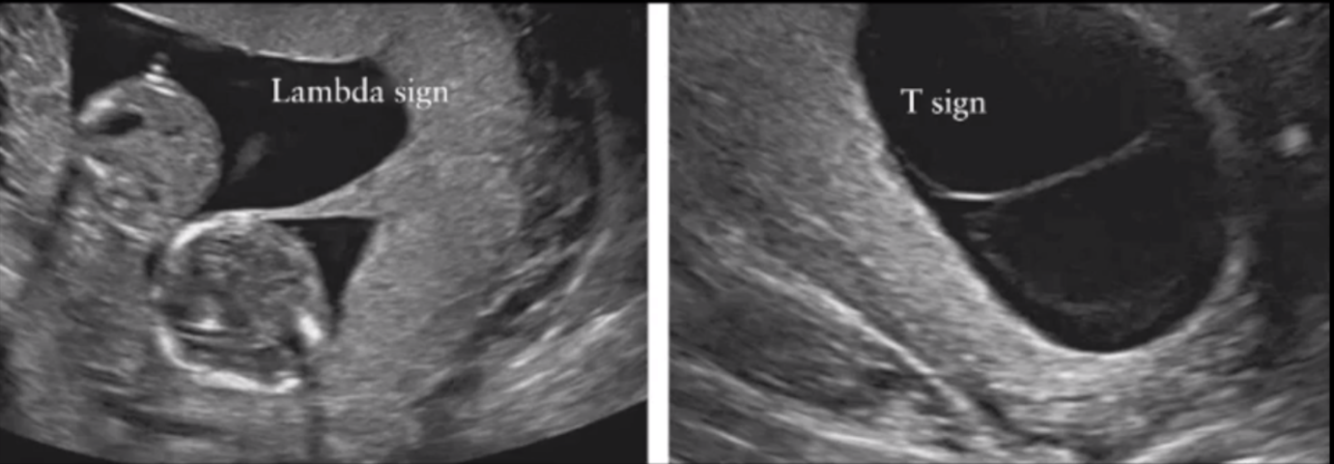

• Determination of zygosity and chorionicity is done by foetal USS

• Lambda sign shows 2 placentas – diagnosing dichorionic diamniotic twins

• T sign shows single placenta – diagnosing monochorionic diamniotic twins

Lambda sign - dichorinic diamniotic twins (2 placentas)

T sign - monochorionic diamniotic twins (1 placenta)